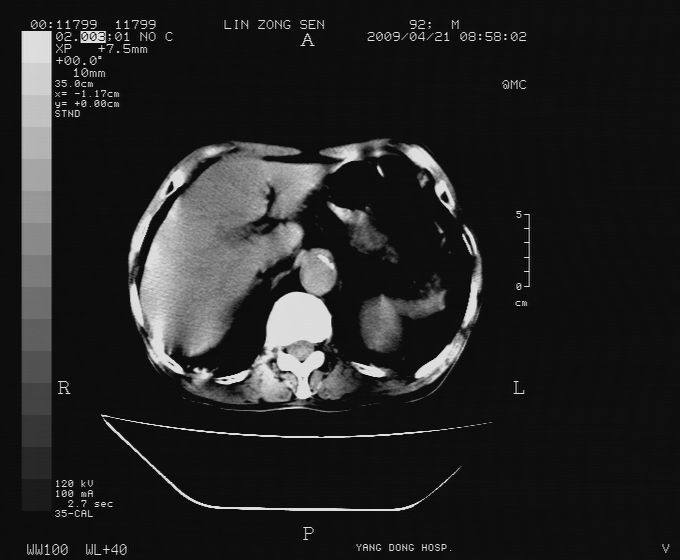

以下是引用卜一在2009-4-22 4:08:00的发言:[br]右肾积水伴输尿管上段积水!左侧肾多发囊肿!左侧腹壁软组织增厚,层次模糊,内密度较高—不排除血管瘤伴出血!